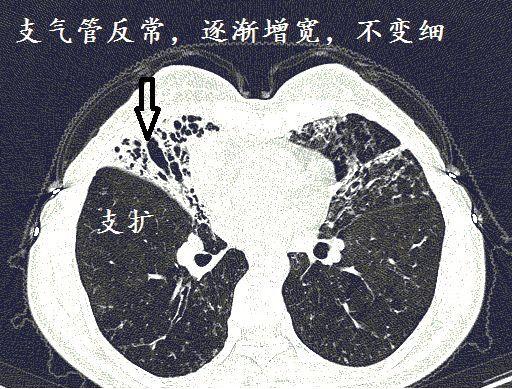

支气管扩张的ct图片

支气管扩张的ct图片,支气管扩张的症状

经典图谱,详细解说支气管扩张ct小诀窍

手把手教你支气管扩张ct诊断

支气管扩张ct图片图解

支气管扩张ct图片

支气管扩张的ct图解

支气管扩张ct图片讲解

支气管扩张ct

支气管扩张双轨征